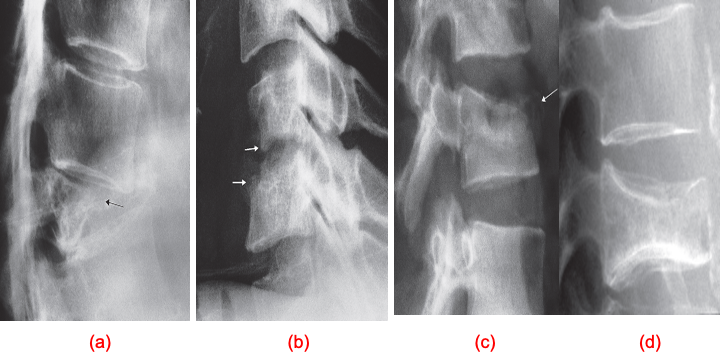

Collapsed vertebra.

(a) Metastasis (arrow) causing complete collapse of the vertebral body. The adjacent vertebral discs are unaffected.

(b) Osteomyelitis. The disc space is narrowed and there is destruction of the surfaces of the adjacent vertebral bodies (arrows).

(c) Traumatic collapse. Note the concave superior surface of the collapsed vertebral body. Some fragments have been extruded anteriorly (arrow).

(d) Osteoporotic collapse. There is decreased bone density with a collapse of a vertebral body due to a compression fracture.